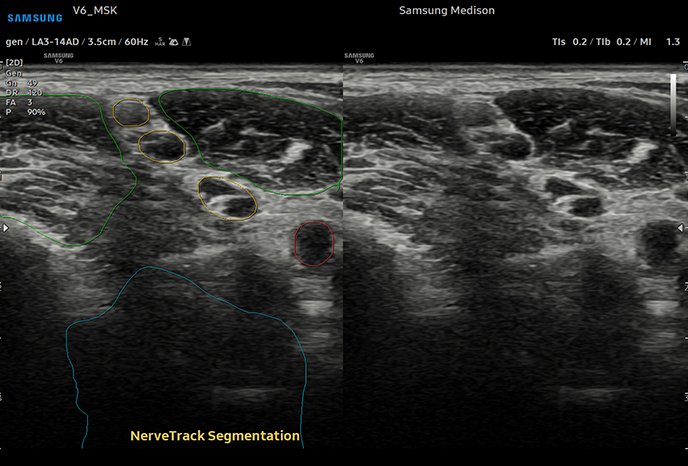

신경 추적

근골격계근골격계 및 관절 인대